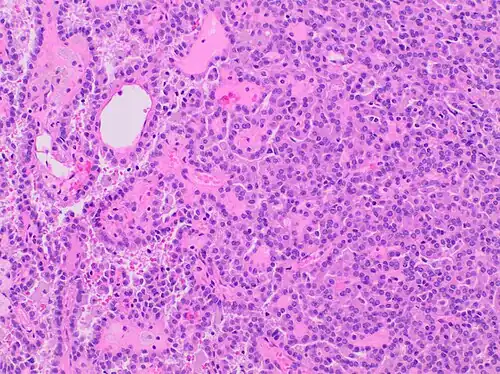

Papillary renal cell carcinoma, type 1, characterised by tubulopapillary architecture with admixed foamy histiocytes in the papillary cores.

Type 1 PRCC, also known as a renal tumor caused by a genetic predisposition of hereditary papillary renal cancer syndrome, compromises approximately 25% of all PRCCs.[14][15] In the perspective of immunochemistry, it has a profile of strong CK7 and alpha-methyl acyl-CoA racemase (AMACR) expression at most focal CA-IX expression.[16] Histologically, its epithelium is composed of relatively small-sized simple cuboidal cells lined in a single layer.[17] These cells are well-characterized by basophilic cytoplasm.[18] Due to its solid growth, an extremely compact papillary architecture is often observed.[16] Other morphological characteristics include intracellular hemosiderin and foamy macrophages placed inside of papillary fibrovascular cores or psammoma bodies.[19] In general, the nuclei of type 1 PRCC belong to grade 1-2 of the Fuhrman system.[16]